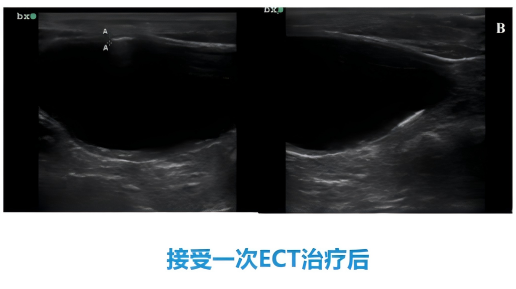

犬膀胱癌

62%的患犬实现完全缓解,24%部分缓解,治疗过程安全,无严重并发症[4];

接受治疗前

接受治疗后